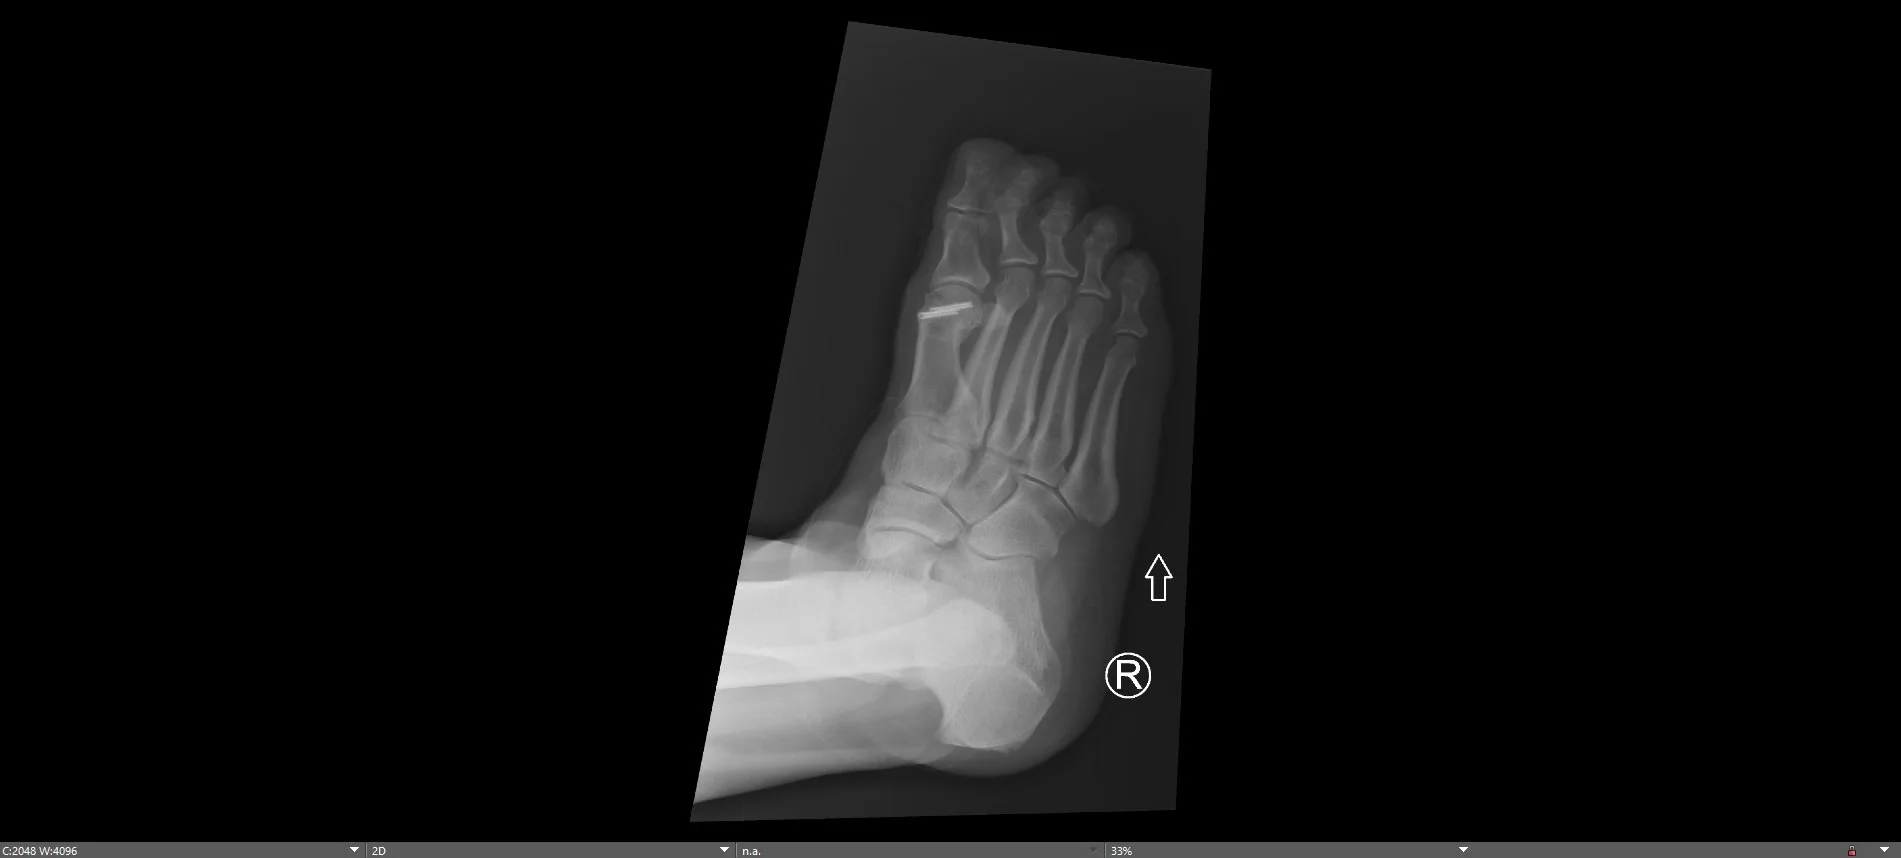

Post-operative xrays demonstrating removal of bone spurs from the 1st metatarsal joint along with osteotomy to decompress the joint surface fixated with 2 headless screws